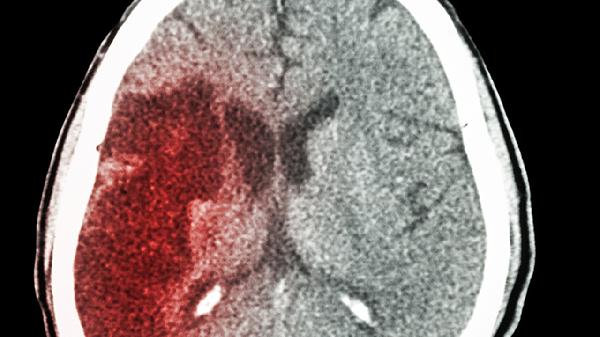

出现喷射状呕吐、抽搐、瞳孔不等大等症状时,可能存在颅内出血,需立即进行头颅CT检查。医生可能根据情况开具甘露醇注射液降低颅压,或使用胞磷胆碱钠胶囊营养神经。